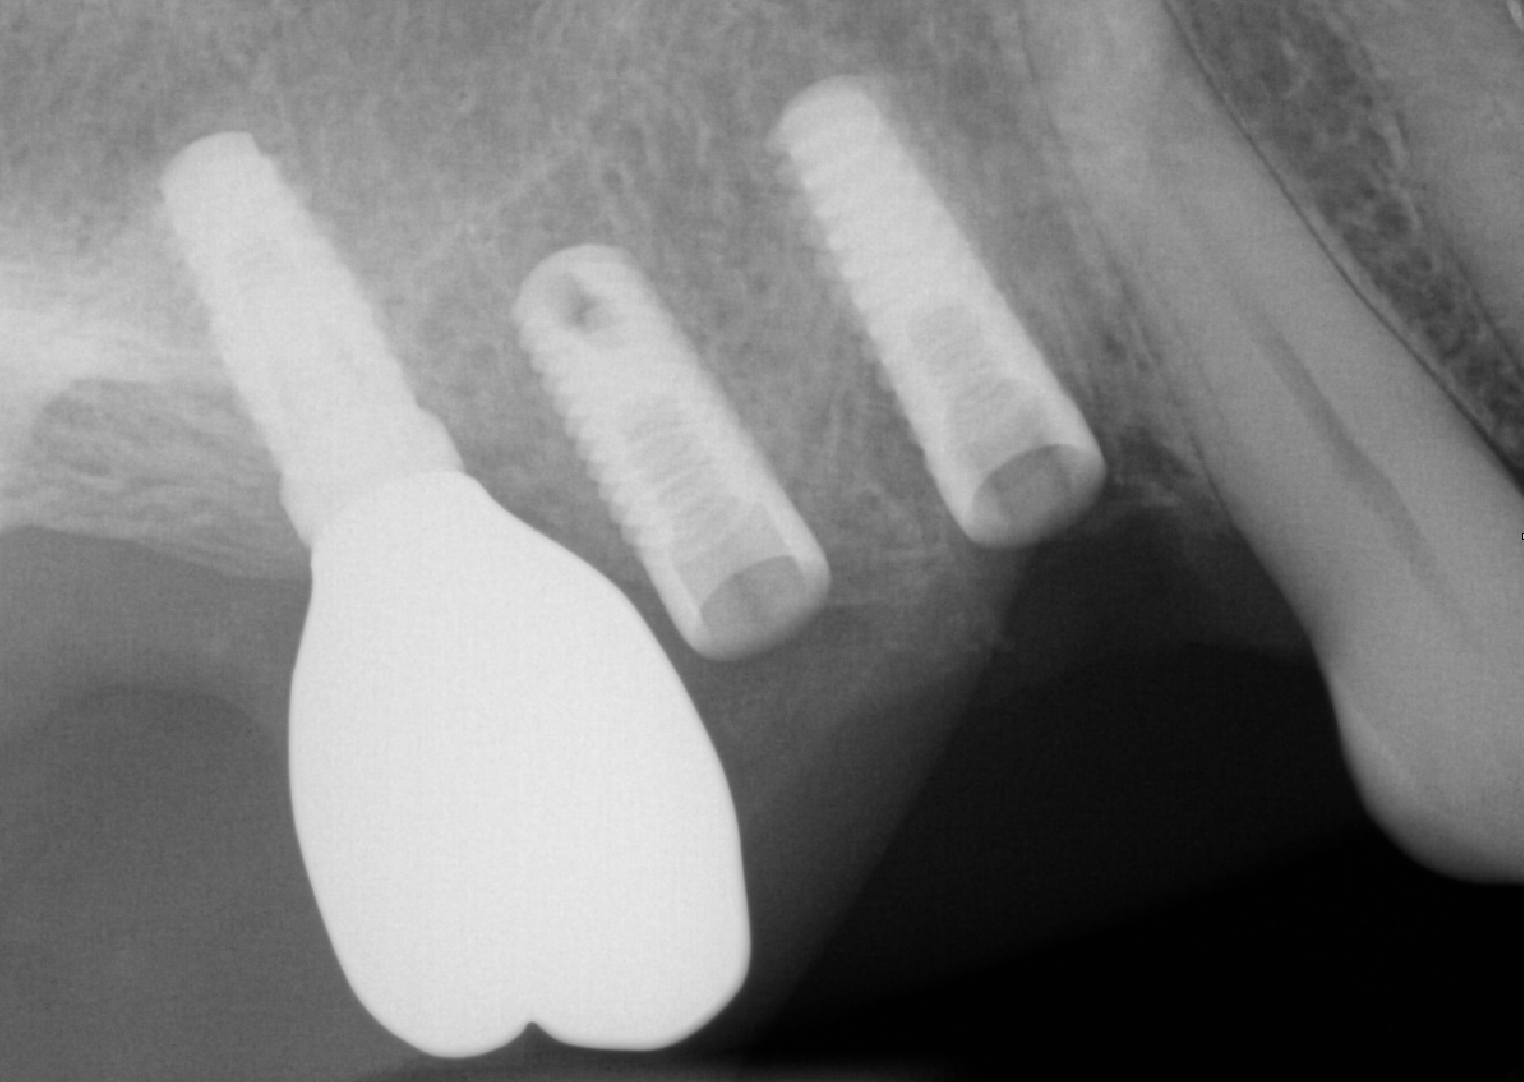

Guided Surgery Same-day Implant Crown